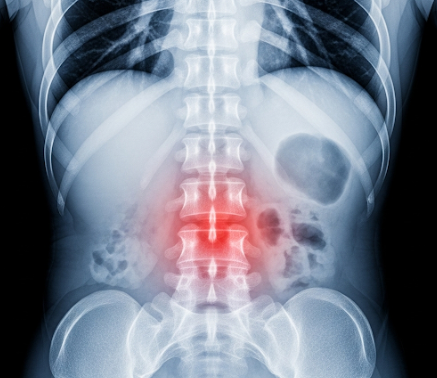

척추관협착증은 척추 내부의 신경이 지나가는 통로인 척추관이 좁아져 신경이 압박되면서 통증과 마비 증상이 나타나는 질환입니다. 노화로 인해 척추뼈와 관절, 디스크 등이 퇴행하면 척추관 내부 공간이 줄어들게 되는데, 이러한 구조적 변화가 척추관협착증의 가장 큰 원인입니다.

퇴행성 변화는 일반적으로 50대 이후부터 시작되며, 60대 이상에서는 발병률이 급격히 증가합니다. 척추를 지지하는 인대가 두꺼워지거나 디스크가 튀어나오는 경우, 혹은 관절이 커지는 등의 변화가 누적되면서 신경통로를 좁히게 됩니다. 이 과정에서 신경이 눌리게 되면 허리 통증뿐 아니라 엉덩이와 다리까지 통증이 퍼지고, 감각이 저하되거나 저림 증상이 생길 수 있습니다.

척추관협착증은 단순한 허리 엑스레이 검사만으로는 명확히 진단하기 어렵습니다. 엑스레이는 척추뼈의 변형 여부를 확인하는 데 도움은 되지만, 척추관 내 신경 압박 상태까지는 볼 수 없습니다. 따라서 MRI 검사가 가장 정확한 진단법으로 활용됩니다. MRI를 통해 척추관의 넓이, 신경 압박 정도, 디스크 상태 등을 정밀하게 파악할 수 있습니다. 필요시 CT나 근전도 검사도 함께 시행됩니다.